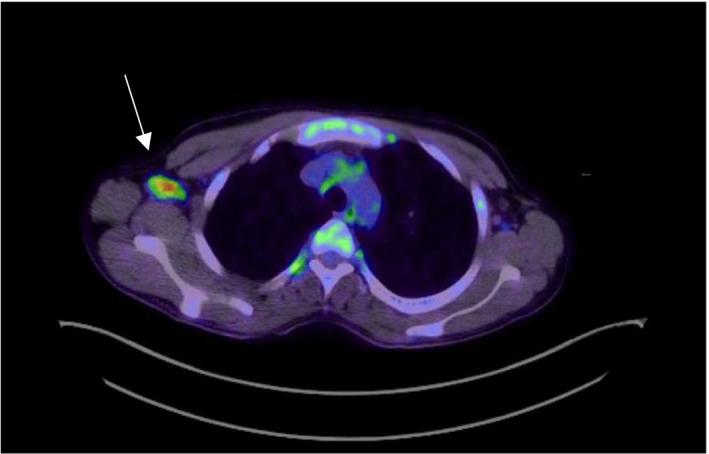

菊池-藤本病的非典型表现:一例病例报告及文献综述

An atypical presentation of Kikuchi-Fujimoto disease: A case report & literature review.

The authors urge clinicians to consider the possibility of Kikuchi-Fujimoto Disease associated with autoimmune hemolytic anemia with possible correlation with systemic lupus erythematosus in patients presented with lymphadenopathy and fever.

摘要